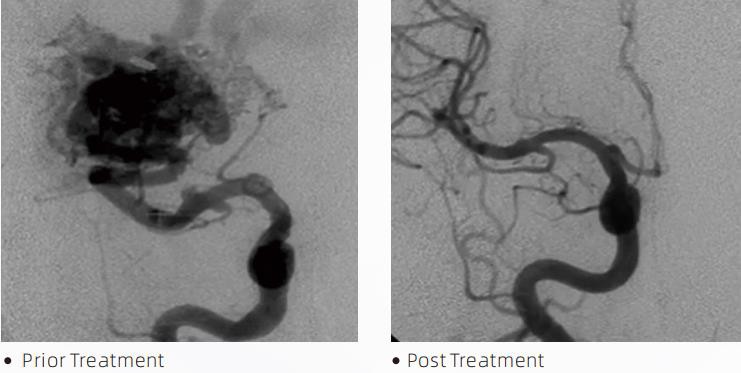

LavaTMSuyuq emboliya tizimi serebrovaskulyar malformatsiyalarni davolash uchun intervensional endovaskulyar terapiyadir. Serebrovaskulyar malformatsiya intrakranial qon ketishiga, miya infarktiga, miya ishemiyasiga va boshqa kasalliklarga olib kelishi mumkin bo'lgan yaxshi yoki xavfli neyrovaskulyar anomaliyalar guruhini anglatadi. Suyuq embolizatsiya tizimi - bu oddiy tomir ichiga yuborish orqali qo'llaniladigan tibbiy asbob bo'lib, u maxsus suyuqlik materialini yuborish orqali g'ayritabiiy miya qon tomirlarini embolizatsiya qiladi. Suyuq moddalar qon tomirlarida nazorat qilinadigan to'qimalar emboliyasini hosil qiladi, bu esa serebrovaskulyar malformatsiyalarning bemorlarga ta'sirini kamaytirishi mumkin. Neyrovaskulaturada foydalanish uchun ko'rsatilgan DMSO mos keladigan etkazib berish mikro kateteri embolizatsiya joyiga kirish uchun ishlatiladi. Lava suyuq embolik agenti DMSO (dimetil sulfoksid) da erigan EVOH (etilen vinil spirti) kopolimeridan va floroskopiya ostida vizualizatsiya uchun kontrastni ta'minlash uchun to'xtatilgan mikronlangan tantal kukunidan tashkil topgan yopishqoq bo'lmagan suyuq embolik agent tizimidir. LavaTMLAVA-12, LAVA-18 va LAVA-34 kabi uchta mahsulot formulasida mavjud. LAVA-12: Distal mikrotomirlarni va kichik oziqlantiruvchilar orqali oziqlantirishda tavsiya etiladi. LAVA-18: Oziqlantirish paytida pedikula in'ektsiyalari nidus yaqinida o'tkaziladi; LAVA-34: Yuqori oqim va kattaroq oqma qismlarini embolizatsiya qilish uchun tavsiya etiladi.